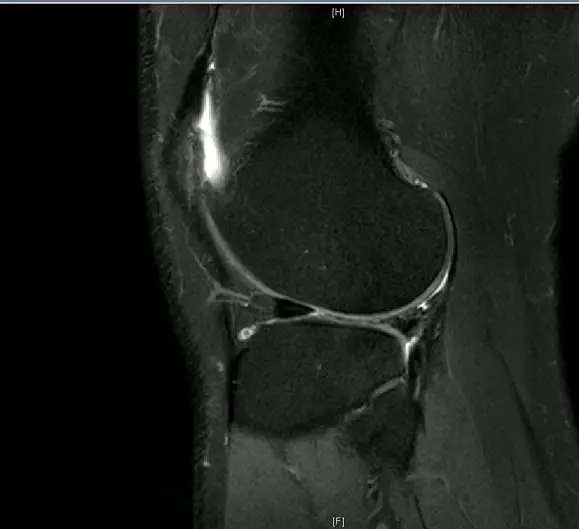

前交叉韧带断裂,外侧半月板后角撕裂

从此片我们可以看到前交叉韧带的上止点高信号,前交叉韧带角度增加,后交叉韧带的夹角增大,从这个层面可以看到外侧半月板边缘不清楚不完整质地不均一,混杂有高信号的改变,并且内部有一些裂隙,从这个层面我们可以看到前交叉韧带的下止点相对比较完整,而这个层面上止点信号异常,韧带松弛并且有大量的渗出病变,缺乏张力。这个层面也可以看到髁间窝这个部位凸起,看不到应有的上止点信号。所以这个病例我们需要考虑前交叉韧带断裂,外侧半月板后角撕裂。